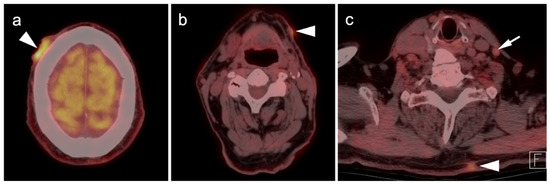

2.3.2. Ocular Melanoma

2.3.3. Mucosal Melanoma

- John, A.R.; Jain, A.; Kishore, B.; Vishnoi, M.; Pandit, A.G.; Sharma, A.; Jaimini, A.; Jain, M.; Singh, A. F-18 fluorodeoxyglucose positron emission tomography/computed tomography in conjunctival melanoma with recurrence. J. Cancer Res. Ther. 2020, 16, 240–242. [Google Scholar] [CrossRef]

- Cassou-Mounat, T.; Luporsi, M.; Huchet, V.; Jehanno, N. Gallbladder Metastasis from Conjunctival Melanoma. Clin. Nucl. Med. 2019, 44, e107–e109. [Google Scholar] [CrossRef]

- Kurli, M.; Chin, K.; Finger, P.T. Whole-body 18 FDG PET/CT imaging for lymph node and metastatic staging of conjunctival melanoma. Br. J. Ophthalmol. 2008, 92, 479–482. [Google Scholar] [CrossRef]